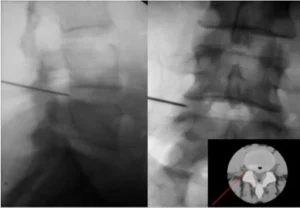

Le procedure di radiologia interventistica per il trattamento dell’ernia del disco sono minimamente invasive e vengono eseguite sotto guida radiologica, garantendo una precisione assoluta. Il radiologo interventista posiziona un ago all’interno del disco intersomatico, utilizzando punti di repere anatomici precisi per assicurare la corretta localizzazione. Per confermare la posizione, è possibile anche iniettare una piccola quantità di mezzo di contrasto radiopaco, una procedura chiamata discografia.

Ernia al disco trattata con tecnica percutanea avanzata

L’immagine mostra il posizionamento dell’ago sotto guida radiologica (fluoroscopia).

Approccio schematico dell’ago all’interno del disco intervertebrale per il trattamento di un’ernia cervicale.

Passaggi intra-procedurali